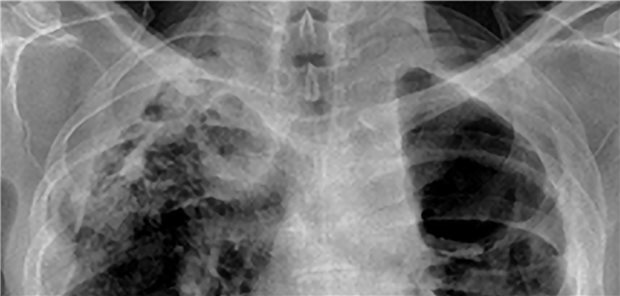

Nach einer frontalen Landung auf dem Wasser hatte ein 22-Jähriger plötzlich nicht nur rechtsthorakale Schmerzen, sondern auch Hämoptysen. Was war die Ursache?

Mitunter verbergen sich ungewöhnliche Erkrankungen hinter scheinbar eindeutigen Lungenbefunden. Zwei Poster mit besonderen Fallberichten, frisch vom Pneumologen-Kongress, veranschaulichen dies.